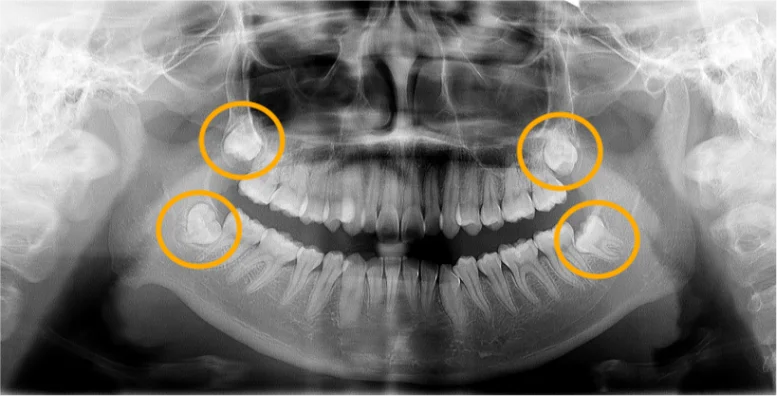

親知らずはお口の中で一番奥にある歯です。 智歯とも呼ばれることもあり、一番前の歯(中切歯)から数えて8番目の歯となります。

親知らずは、斜めや横向きに生えることが多く、ときには歯ぐきの炎症や痛みの原因になることもあります。

親知らずはこのように横向きに生えることが多いです。 横向きに生えた親知らずは手前の歯をグイグイと押し、歯並びに悪影響を与えることがあります。

親知らずが原因で含歯性嚢胞(がんしせいのうほう)などの嚢胞や腫瘍ができる可能性があります。